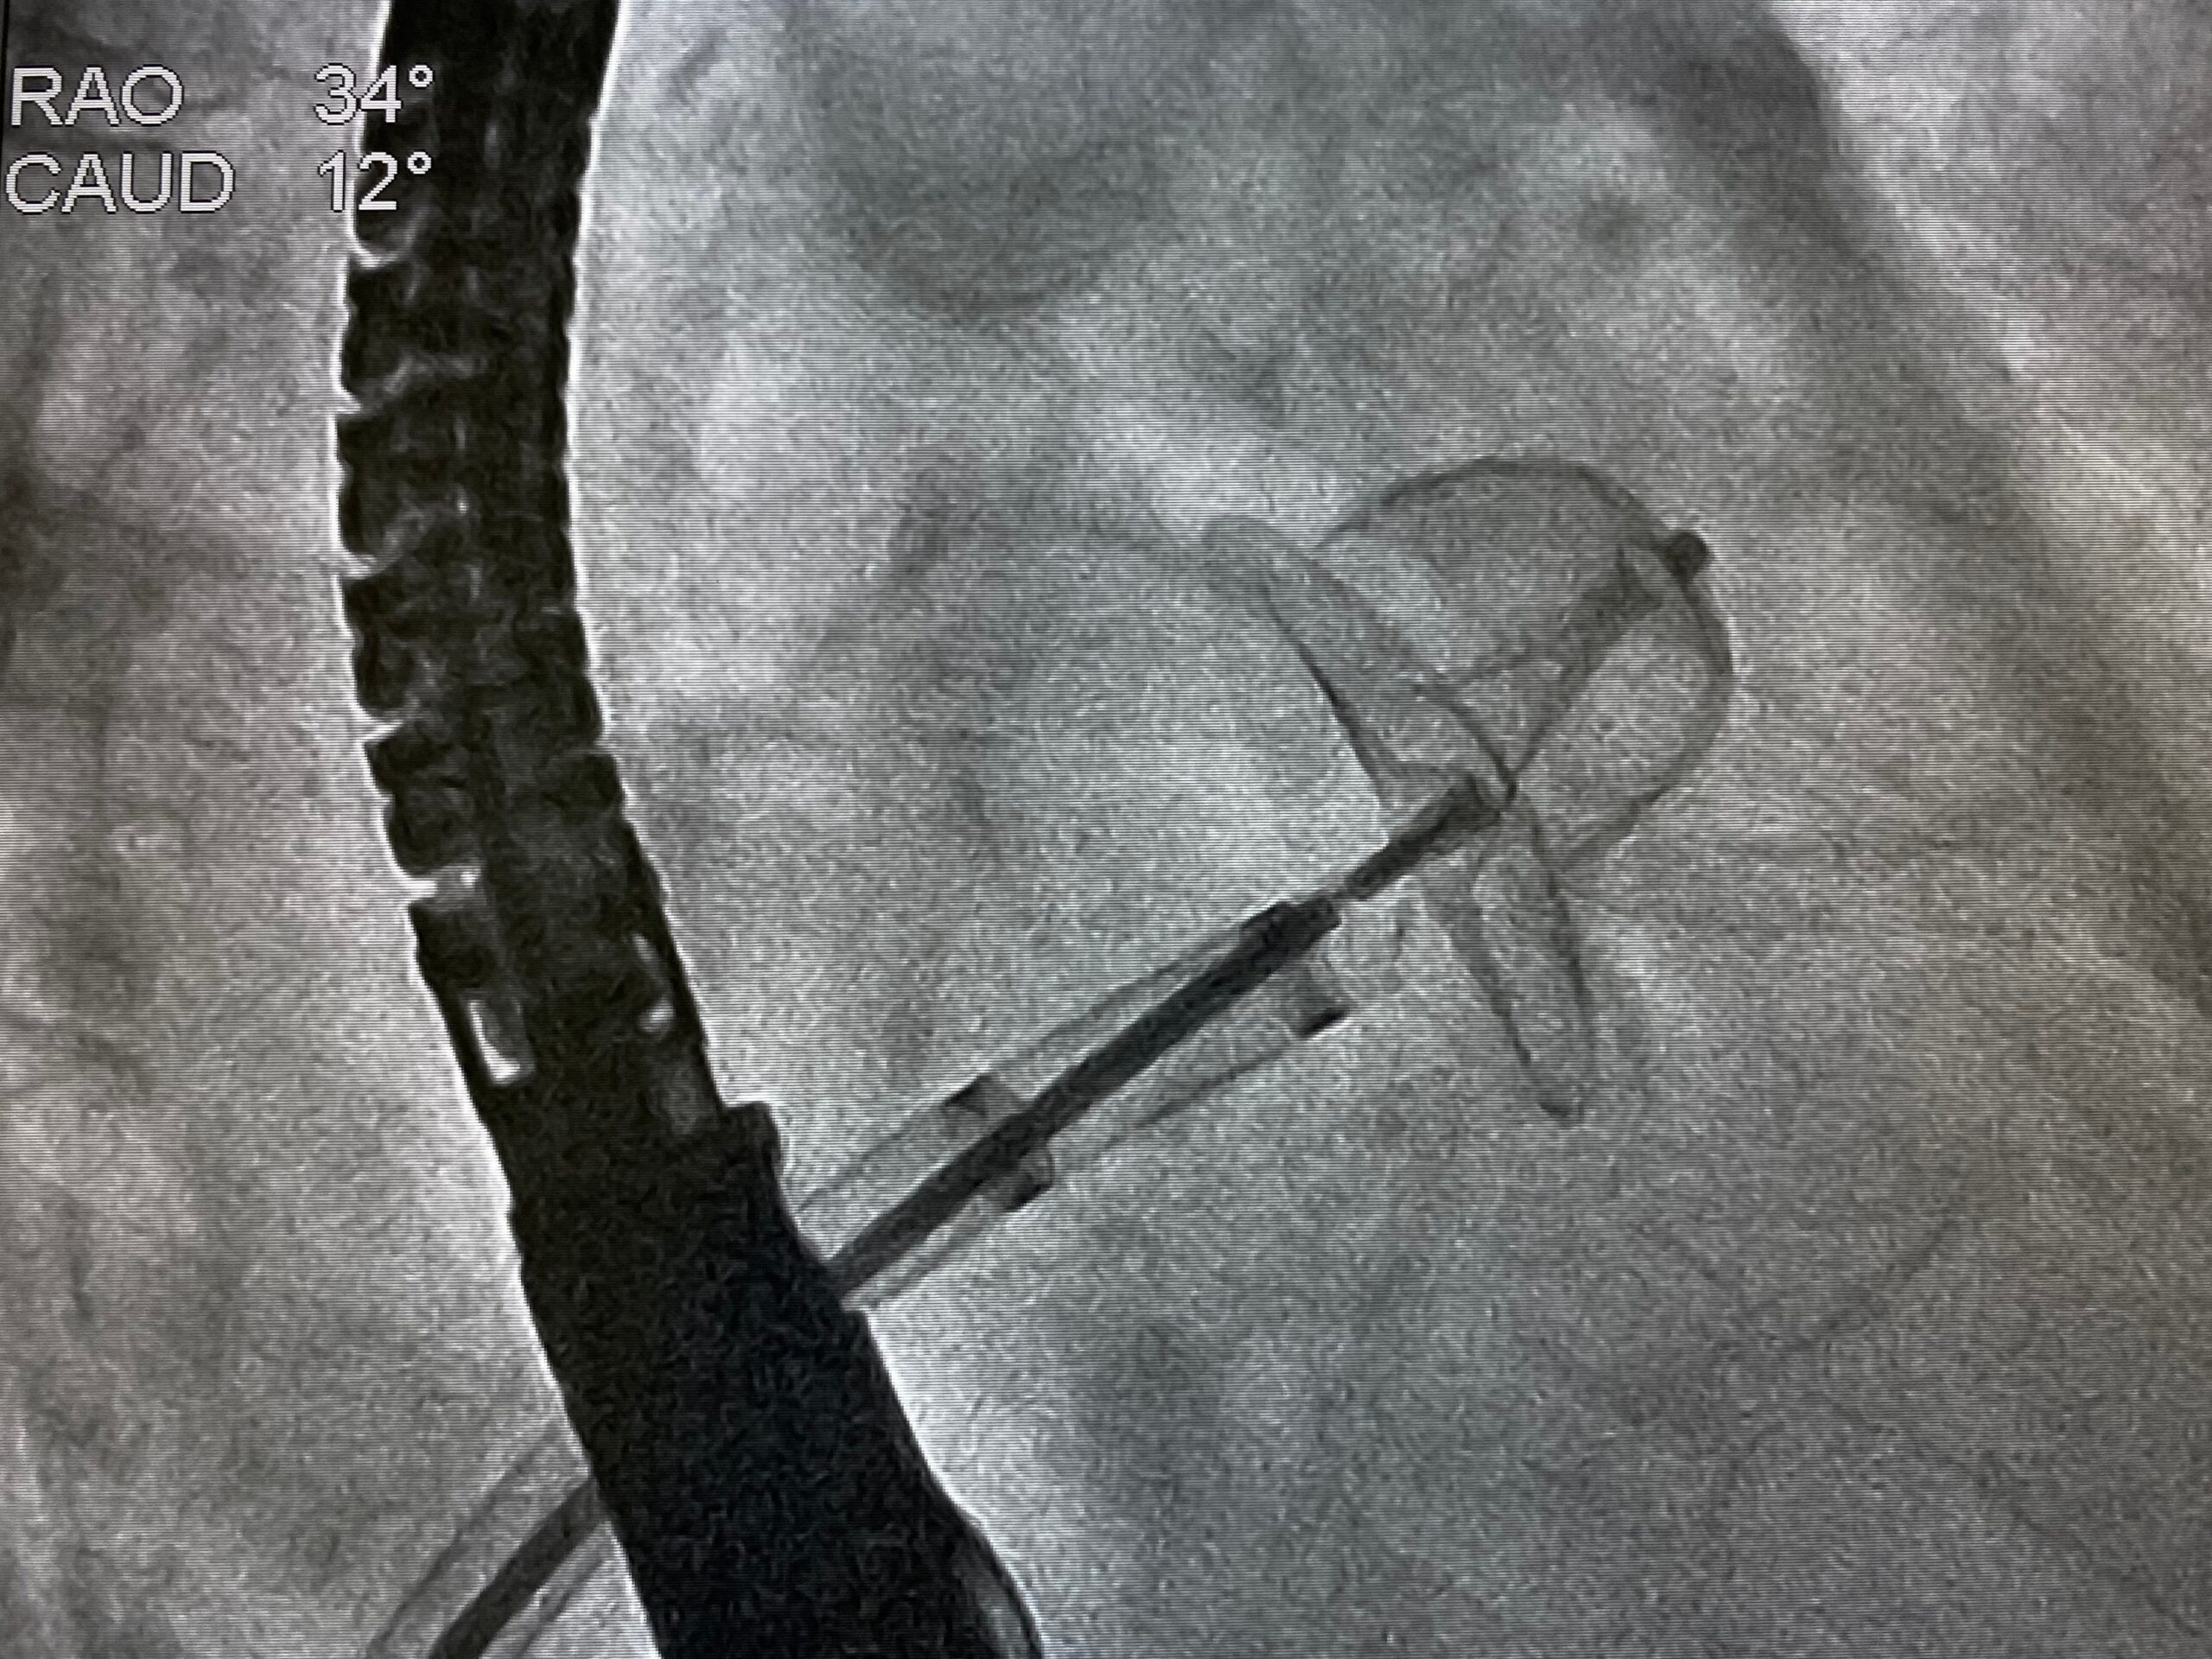

LAAO in elderly patients with atrial fibrillation demonstrates similar efficacy to those seen in younger patients.